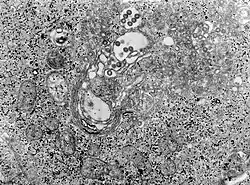

TEM micrograph of tissue infected with Rift Valley fever virus